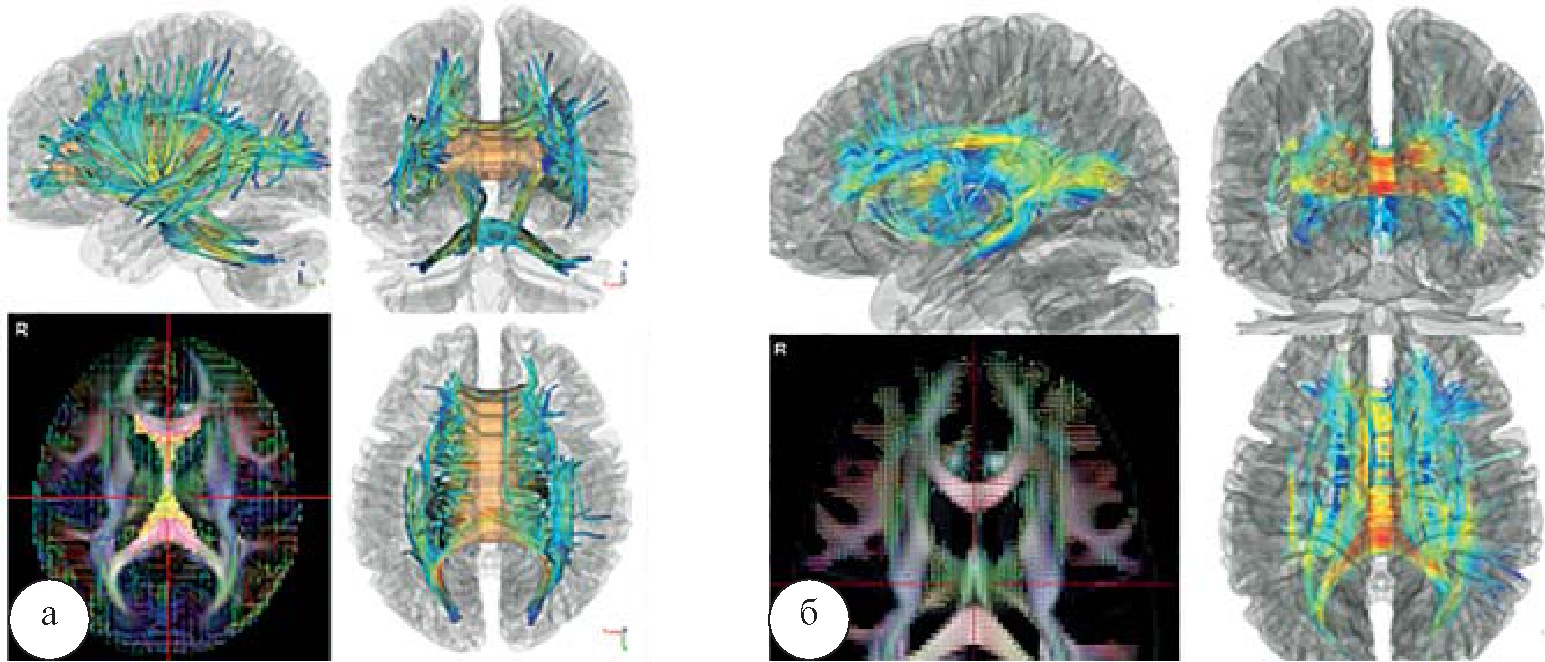

Результаты межгрупповой магнитно-резонансной коннектометрии у пациентов, страдающих зависимостью от опиоидов, демонстрируют значительное снижение коэффициента GFA в трактах, исходящих из мозолистого тела к поясной извилине и к структурам мозжечка (рис. 7).

Рис. 7. Особенности микроструктурной организации между полушариями головного мозга: а – при синдроме зависимости от опиоидов; б – у больных, страдающих алкоголизмом, p<0,05. О снижении GFA свидетельствуют холодные цвета, о повышении – теплые

При межгрупповом анализе между пациентами, страдающими синдромом зависимости от алкоголя и нормой, было выявлено уменьшение фракционной анизотропии в кортикоталамическом пучке справа, и парадоксальное ее увеличение в мозолистом теле (pFDR<0,07), что свидетельствует об особенностях микроструктурной организации между полушариями головного мозга у больных, страдающих синдромом зависимости от алкоголя.

Снижение GFA в кортикоталамическом пучке, связывающем МПФК с системой таламуса, еще раз подкрепляет наше предположение, сделанное на основе нейрофункциональных данных, о снижении контролирующего влияния коры над эмоциогенными структурами.